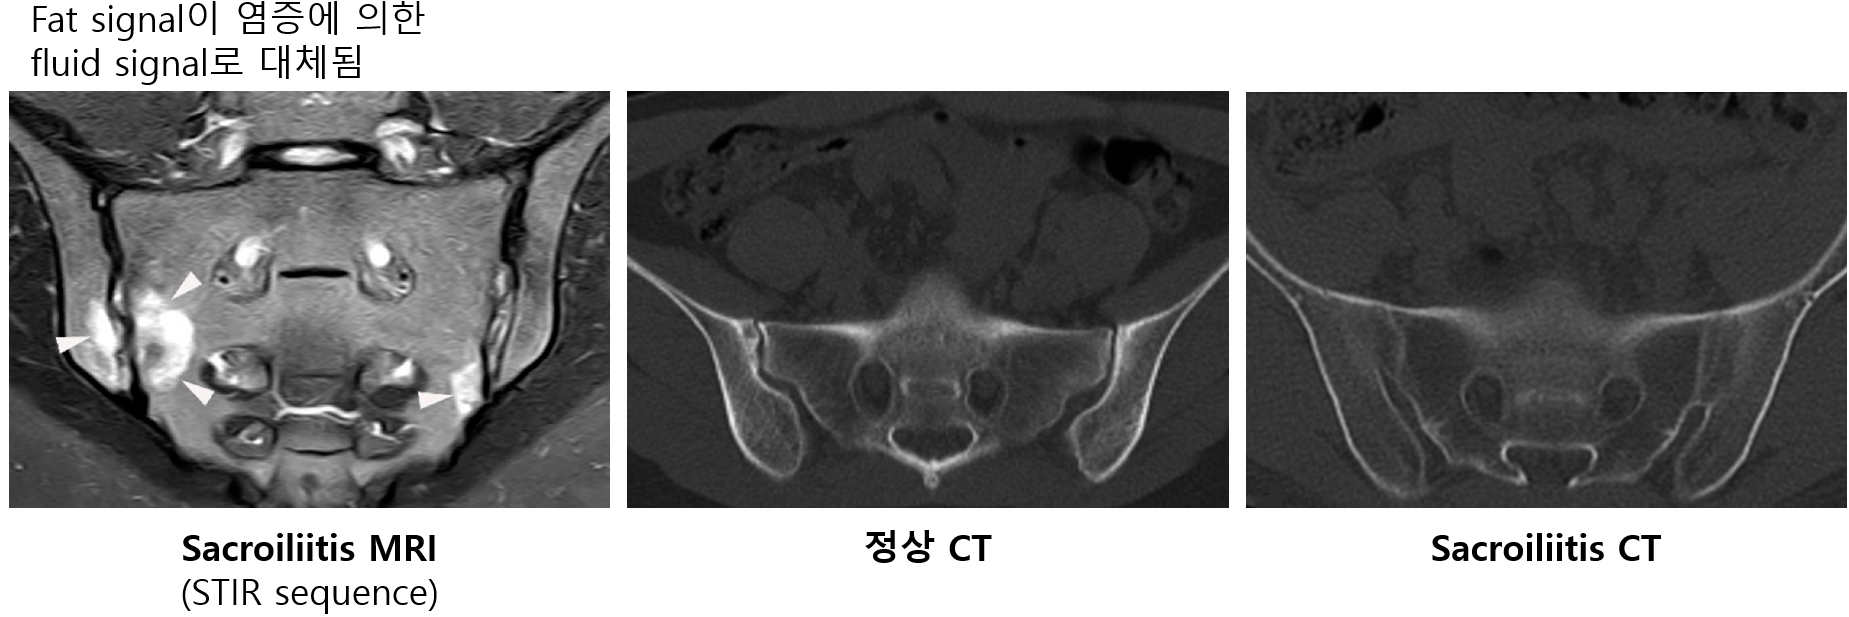

(2) 골반 MRI/CT: X-ray로 진단이 어려울 때 시행

(1) 골반 X-ray: 엉치엉덩관절염(sacroiliitis) 확인 (grade 0~4로 분류)

• Subchondral 피질 경계가 흐려짐 → erosion and sclerosis → joint obliteration